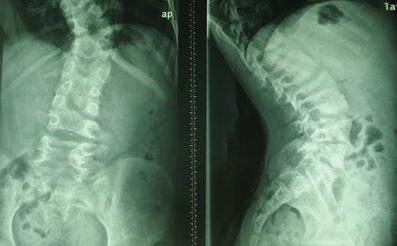

因长期开长途车,章先生经常感觉到腰酸背痛。一次突如其来的疼痛将章先生折磨得脸色煞白,上衣已经被汗水浸湿,后被送到到当地的诊所就诊,确诊为强直性脊柱炎。经过多次治疗无效后来到我院接受治疗。...[详细]

周先生在夜间执勤时不慎遭不明盗窃团伙实施犯罪遭殴打,伤到后腰,一星期后发展为腰部剧烈疼痛,坐立、行走都很困难。经综合医院确诊为强直性脊柱炎,经多方推荐,周先生来到我院接受治疗。...[详细]